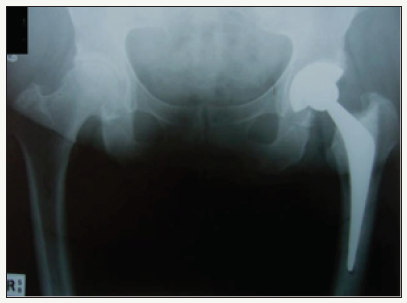

A 70 year old male underwent right total hip arthroplasty for osteoarthritis (Figure 6). A 56mm Pinnacle sector 2 acetabular cup was inserted with a neutral Marathon polyethylene liner (28mm ID x 56mm OD) and mated via a 28mm+5 high offset stainless steel Articul/Eze femoral head (12/14 cone) to an uncemented No 11 Corail stem. Post-op recovery was uneventful. Post-op X-Rays showed 46° of inclination of the cup (Figure 7).

figure 7: Post-op right total hip arthroplasty.